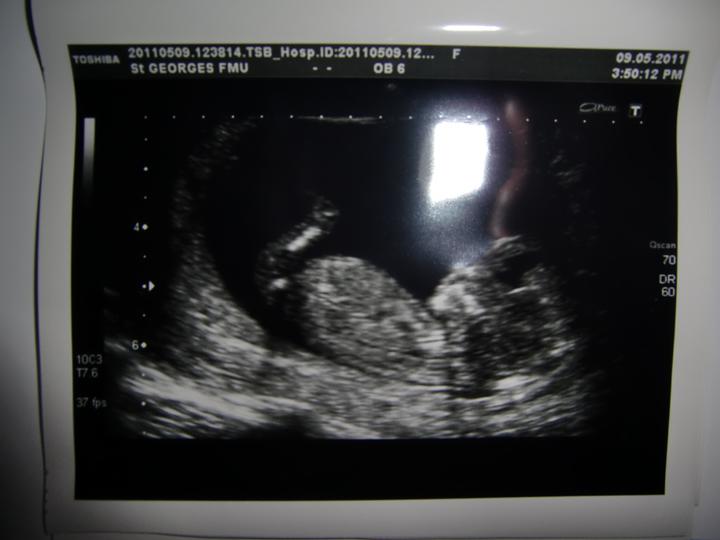

Bol to najuzasnejsi den, vsetko dopadlo nad nase ocakavania. Sme velmi radi ze si to na slovensku mozme zase zopakovat v auguste v kosiciach...